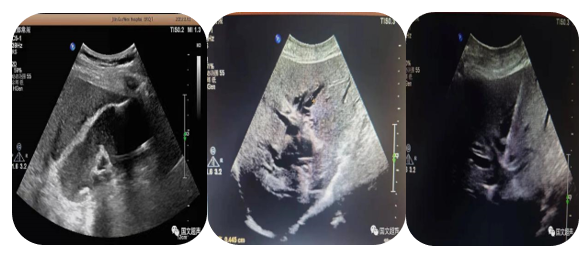

3.超聲引導(dǎo)下經(jīng)皮經(jīng)肝膽道置管引流、膽囊造瘺;經(jīng)皮腎造瘺、膀胱造瘺

超聲實時引導(dǎo)下將引流管放置在因腫瘤、結(jié)石等壓迫、堵塞梗阻擴張的膽道、腎盂、膽囊、膀胱內(nèi)引流出潴留的膽汁、尿液,防止或緩解肝腎功能衰竭,進而減緩患者痛苦為臨床爭取治療機會。

經(jīng)皮經(jīng)肝膽囊造瘺、膽道置管引流

經(jīng)皮腎造瘺

經(jīng)皮膀胱造瘺